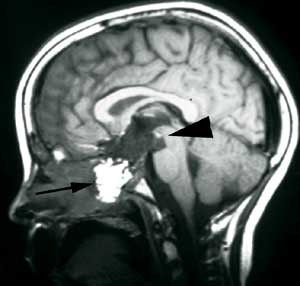

Pasient 1. Ni år gammel pike, født til termin, upåfallende psykomotorisk utvikling. Fra sju års alder klaget hun periodevis over svie/kløe i begge øynene og dobbeltsyn. Hun ble da bredt utredet uten resultat. Symptomene gikk delvis tilbake, men påfølgende år tilkom økende symptomer og man påviste da en bilateral abducensparese. Ny bildediagnostikk avslørte nå en stor ekspansiv prosess utgående fra clivus med affeksjon av pons, mest forenlig med et clivuskordom (fig 2a).

Det postoperative forløpet var meget tilfredsstillende. Hun kunne mobiliseres første dag etter inngrepet uten nye nevrologiske utfall. En postoperativ MR avslørte en liten resttumor (fig 2b). Hun ble derfor henvist og behandlet ved Stråleknivenheten, Nevrokirurgisk avdeling, Haukeland Universitetssykehus. Påfølgende år har hennes dobbeltsyn vært i jevn bedring. MR-kontroller har vist at resttumor er i regresjon.